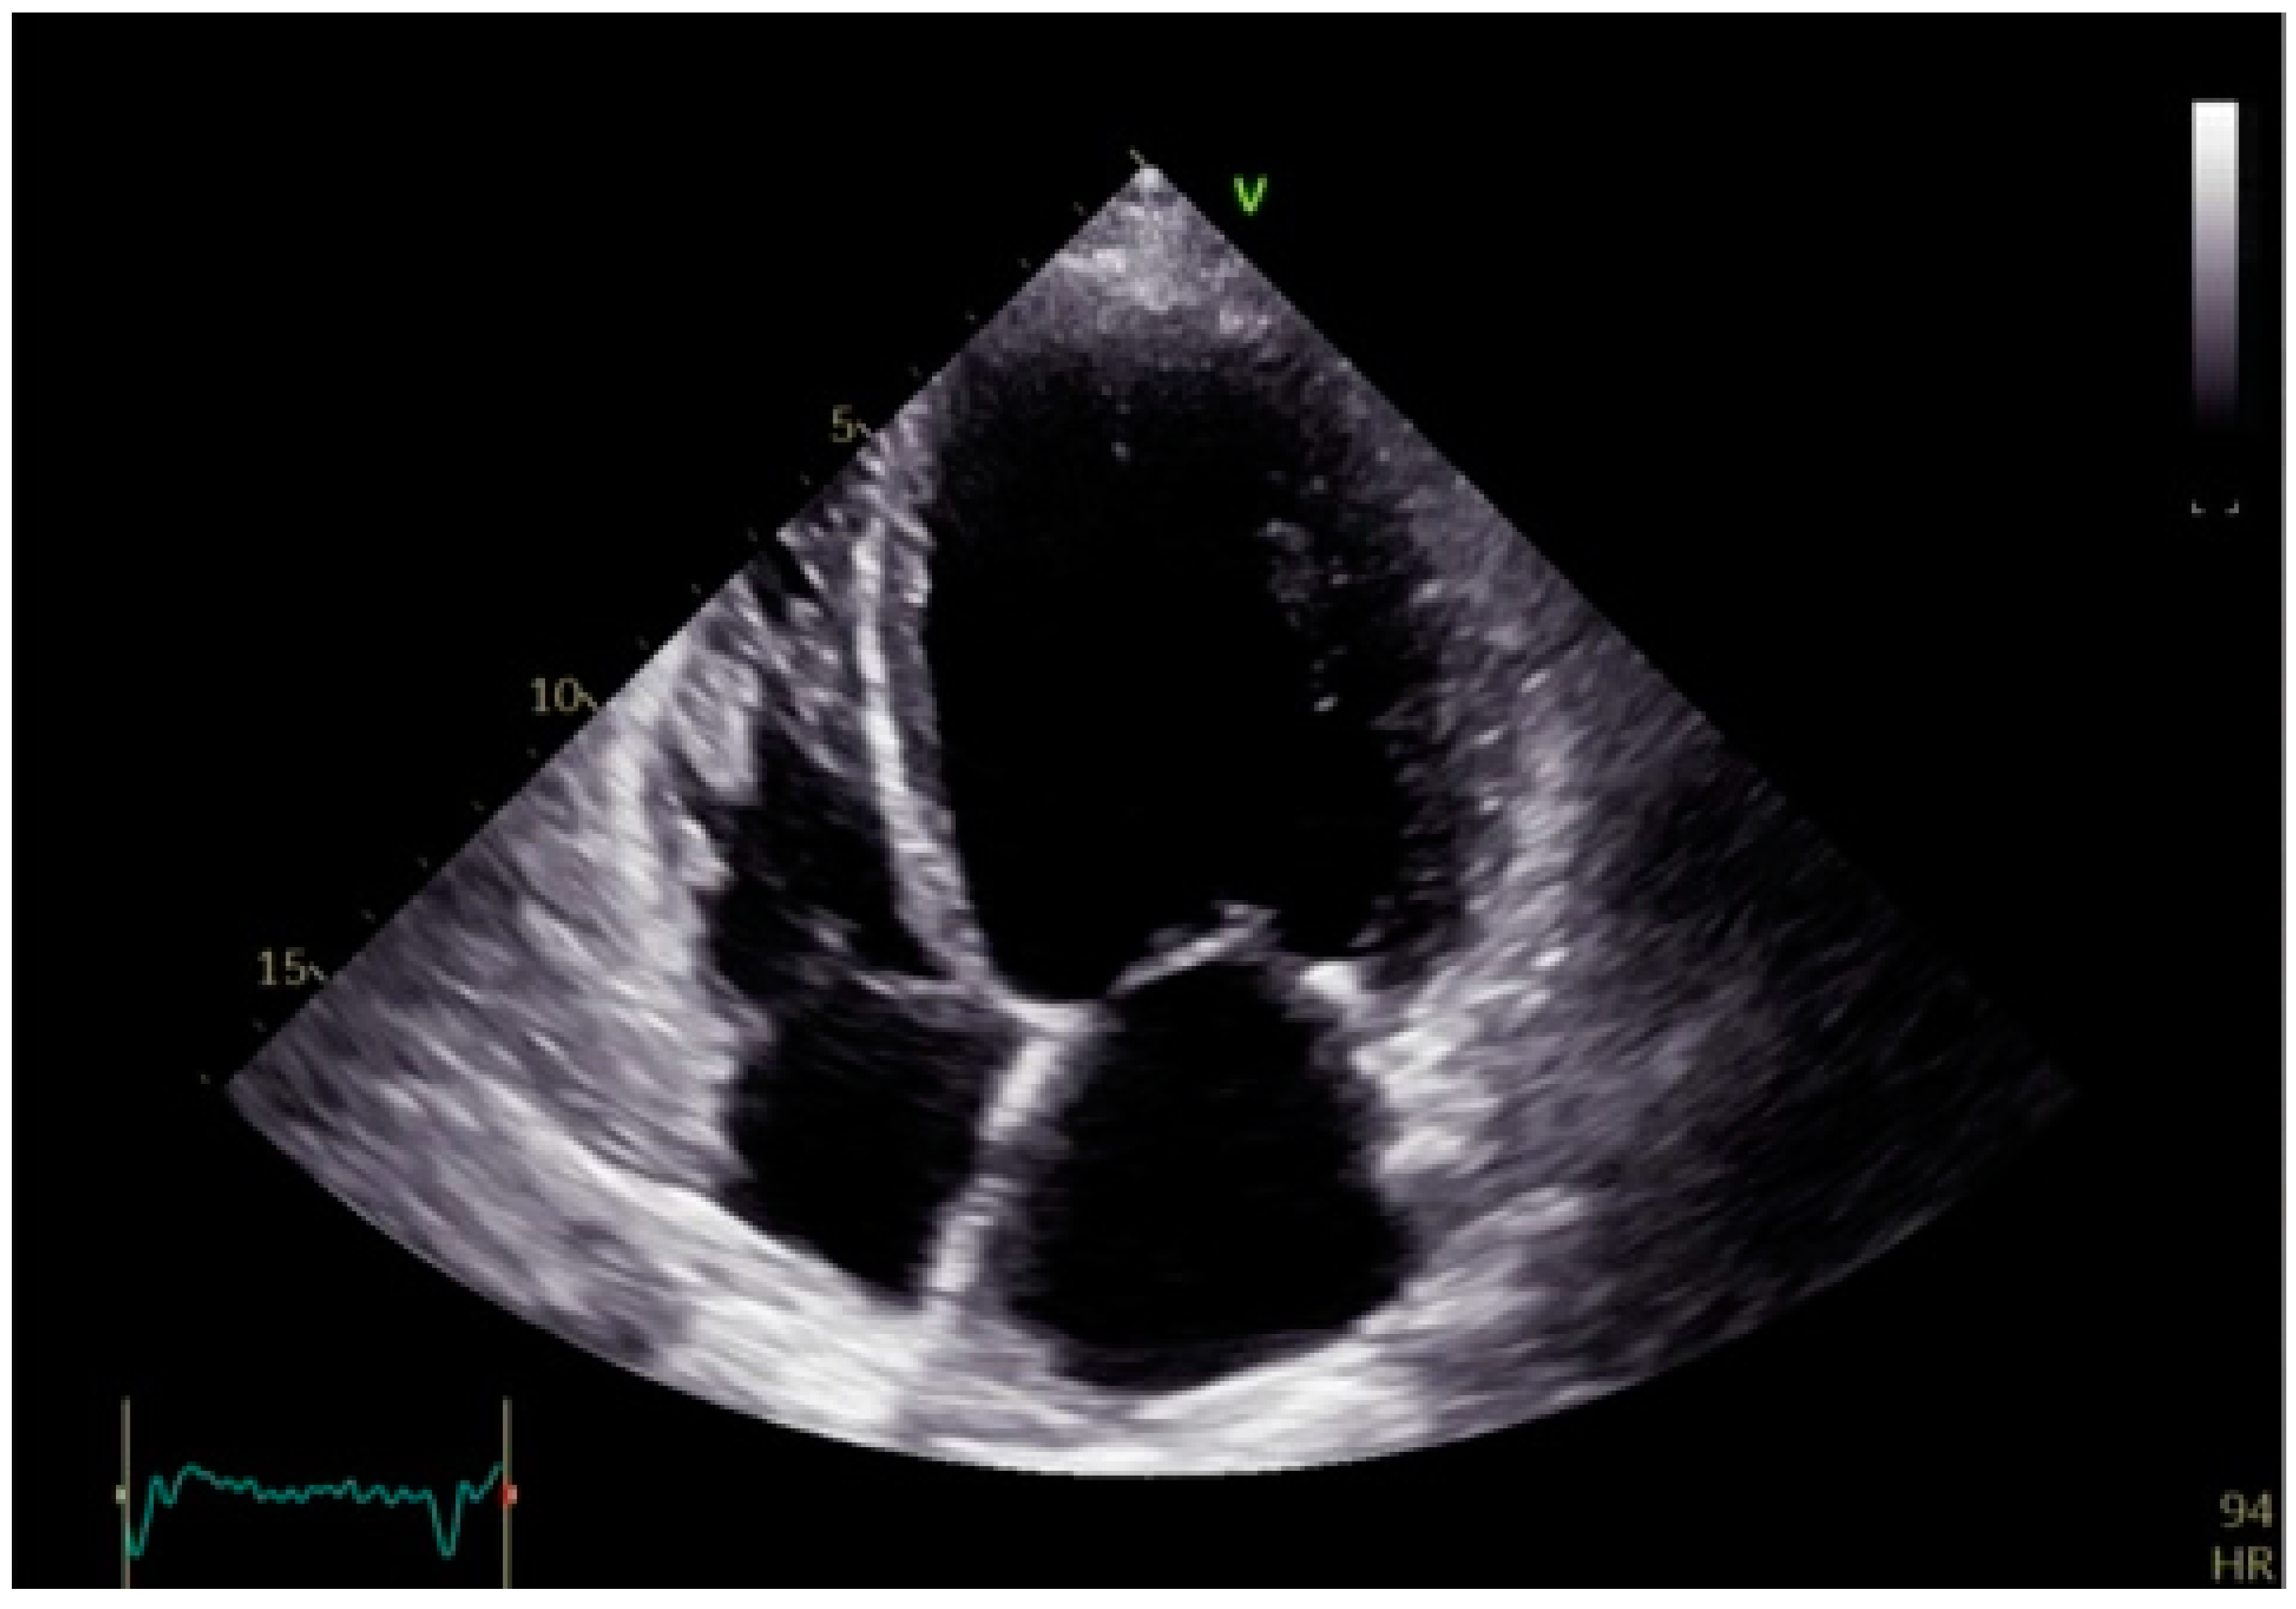

Over time, the increased workload and wall stress lead to adverse remodeling, including left ventricular dilation, hypertrophy, and fibrosis (Figure 4). These structural changes further deteriorate heart failure symptoms, heighten arrhythmic risk, and contribute to poor clinical outcomes [13].

Figure 4. Apical four-chamber echocardiographic view showing dilated left ventricle with a fibrotic interventricular septum, characterized by increased echogenicity and reduced mobility, suggestive of structural remodeling.